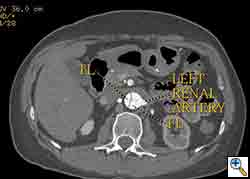

The patient was taken to the hybrid operating suite and a thoracic aortogram was performed. The aortogram confirmed the chronic Type B aortic dissection with a patent false lumen and a fenestration just beyond the left subclavian artery. An intravascular ultrasound (IVUS) was also performed of the entire aortic arch and descending thoracic and abdominal aorta. The IVUS also confirmed that there was an adequate proximal landing zone beyond the left subclavian artery consisting of normal aorta where we would be able to achieve adequate seal of the endovascular stent graft. The septal fenestration began approximately 1.5 cm distal to the left subclavian artery. The true lumen was compressed distally. (Figure 2) The celiac artery appeared to come off the true lumen. (Figure 3) The dissection extended into the superior mesenteric artery and the artery was perfused from both the true and false lumen. (Figure 4) The left renal artery came off the false lumen. (Figure 5) The right renal artery came off the true lumen.